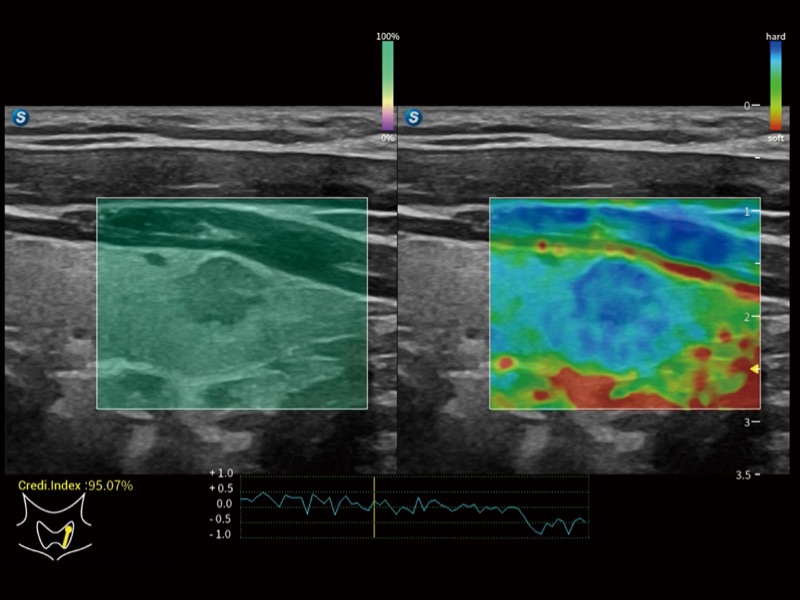

便携式彩色多普勒超声诊断系统

作为开立医疗全新打造的高端全域笔记本超声,X11集成了当前先进的硬件架构和精密的设计工艺,提升多科室临床医生在常规影像检查中的诊断能力,为临床提供全面的诊疗支持。